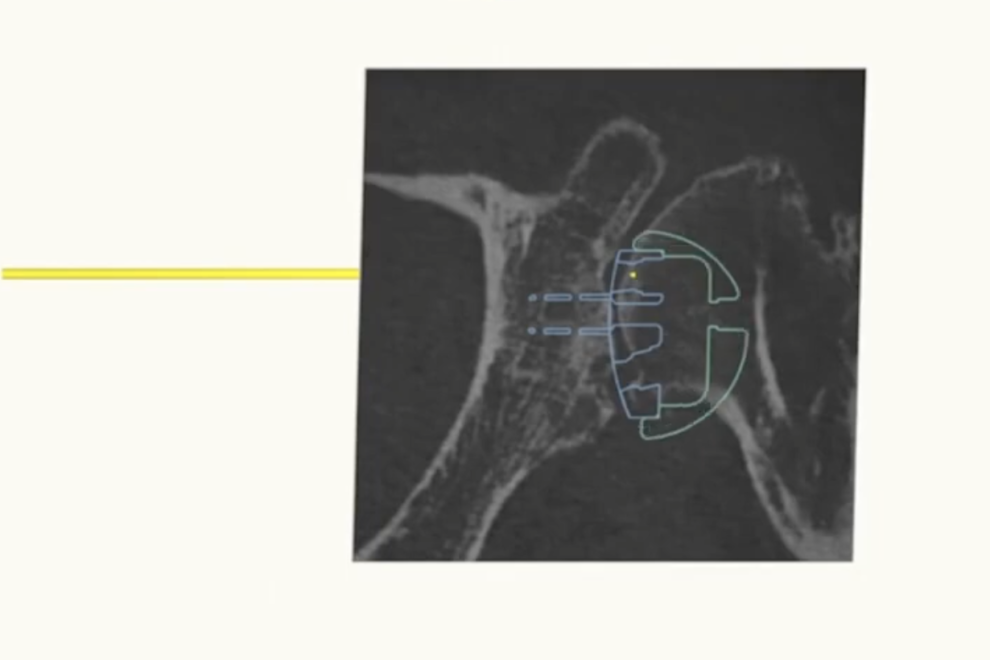

Che esami fare per dolore alla spalla? Guida completa per una diagnosi accurata Il dolore alla spalla è un disturbo comune che può colpire persone di tutte le età e livelli di attività. Può derivare da diverse cause, come traumi, infiammazioni o problemi articolari. Tuttavia, per trattare efficacemente il problema, è fondamentale comprendere la causa…